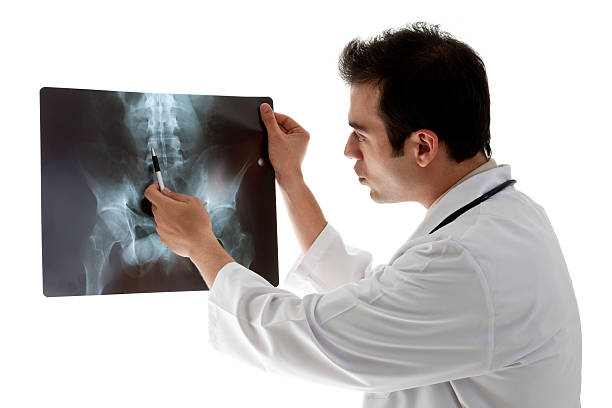

요추 염좌가 발생했을 때, 가장 중요한 것은 휴식과 냉찜질입니다. 빠른 회복의 지름길입니다.

허리에 보조기를 사용하는 것은 급성 통증을 완화하는 데 도움이 될 수 있지만, 장기적으로 보조기에 의존하면 근육이 약해질 수 있으므로 통증이 사라진 후에는 보조기를 풀고 꾸준한 운동을 하는 것이 좋습니다.

만성 허리 통증은 방치하면 심화될 수 있으므로 적절한 치료를 받는 것이 중요합니다. 만성 통증은 한 번에 해결되지 않고 악화와 개선이 반복될 수 있으므로 주의가 필요합니다.

요추 염좌의 원인은 비만, 무리한 운동, 자세 등 다양한 요인과 관련이 있으므로 건강한 생활 습관과 적절한 운동이 필요합니다.

요약하면, 허리 통증과 요추염좌는 일상생활에서 흔히 겪을 수 있는 문제이며, 적절한 치료와 예방을 통해 건강한 척추를 유지하는 것이 중요합니다. 만약 통증이 심하다면 전문의의 도움을 받아보는 것이 좋습니다.